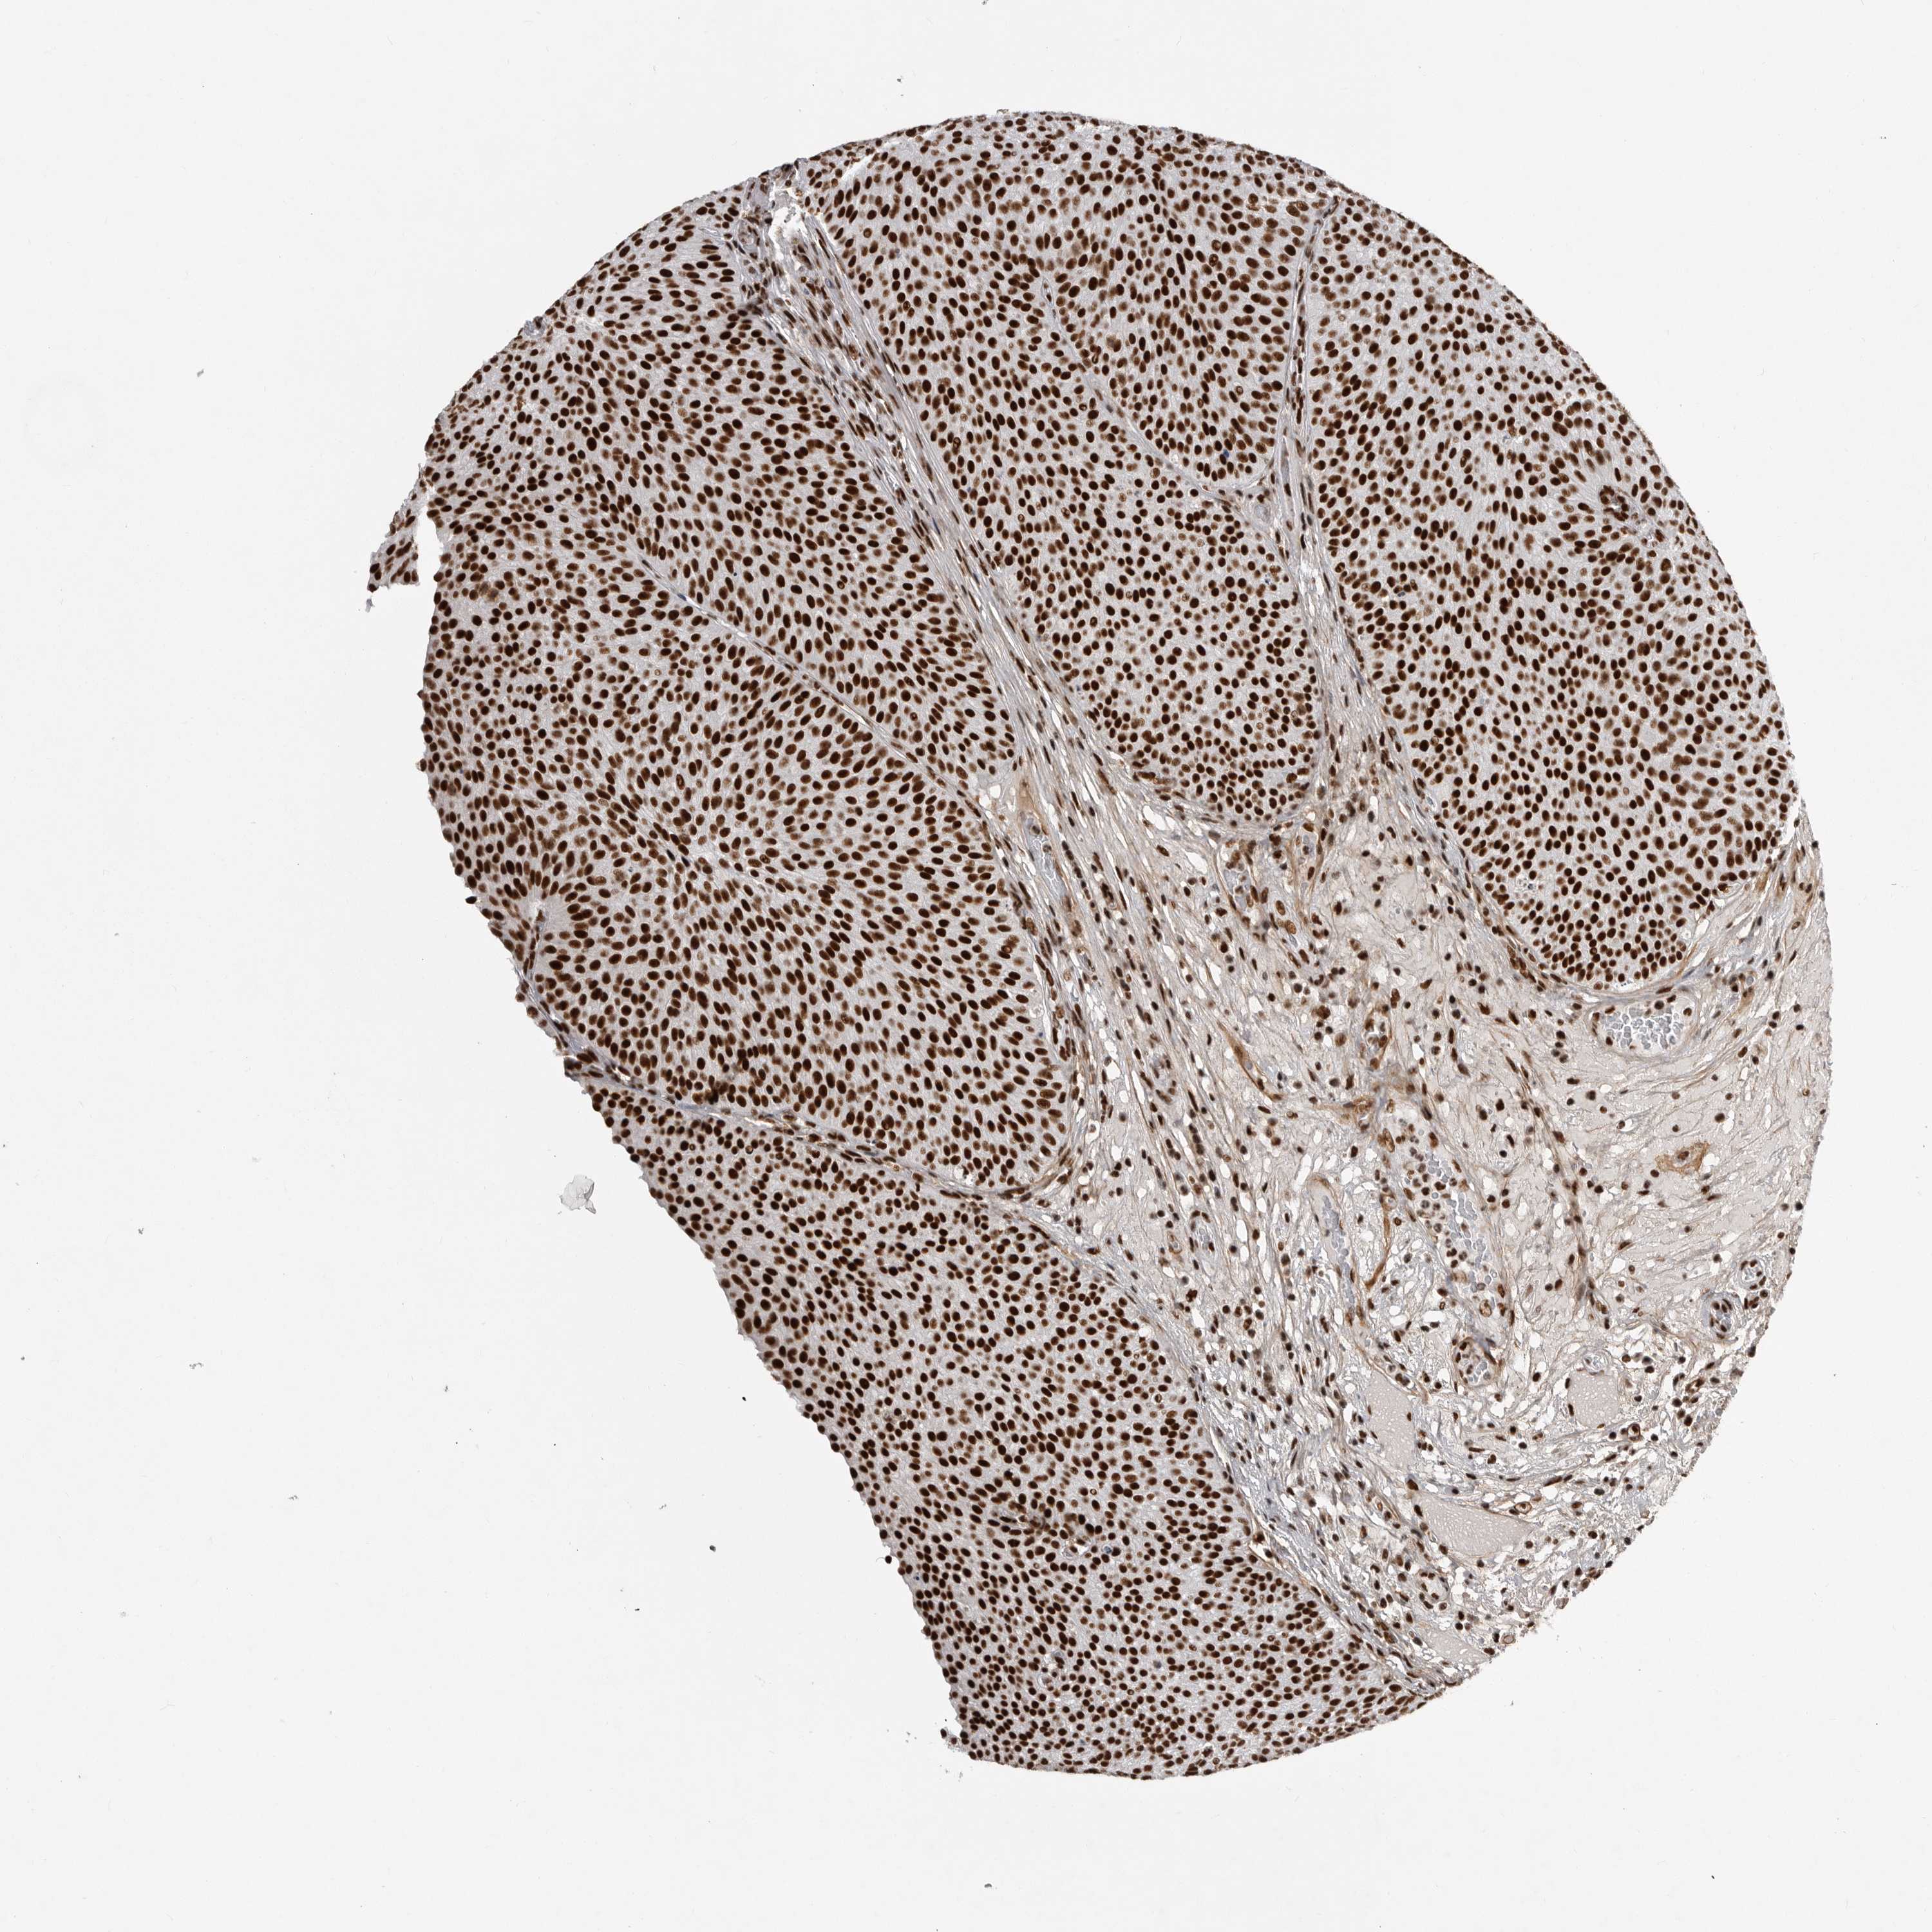

UROTHELIAL CANCER - Protein expressioni

A mouse-over function shows sample information and annotation data. Click on an image to view it in a full screen mode. Samples can be filtered based on level of antibody staining by selecting one or several of the following categories: high, medium, low and not detected. The assay and annotation is described here.

Note that samples used for immunohistochemistry by the Human Protein Atlas do not correspond to samples in the TCGA dataset.

Antibody stainingi

Antibody staining in the annotated cell types in the current human tissue is reported as not detected, low, medium, or high, based on conventional immunohistochemistry profiling in selected tissues. This score is based on the combination of the staining intensity and fraction of stained cells.

Each image is clickable and will lead to virtual microscopy that enables deeper exploration of all samples and also displays staining intensity scores, fraction scores and subcellular localization as well as patient and tissue information for each sample.

Antibody HPA027406

Antibody HPA027417

Antibody HPA027452

Staining

High

Medium

Low

Not detected

Intensity

Strong

Moderate

Weak

Negative

Quantity

>75%

75%-25%

<25%

None

Location

Nuclear

Cytoplasmic/membranous

Cytoplasmic/membranous,nuclear

Urothelial carcinoma, Low grade

Urothelial carcinoma, High grade